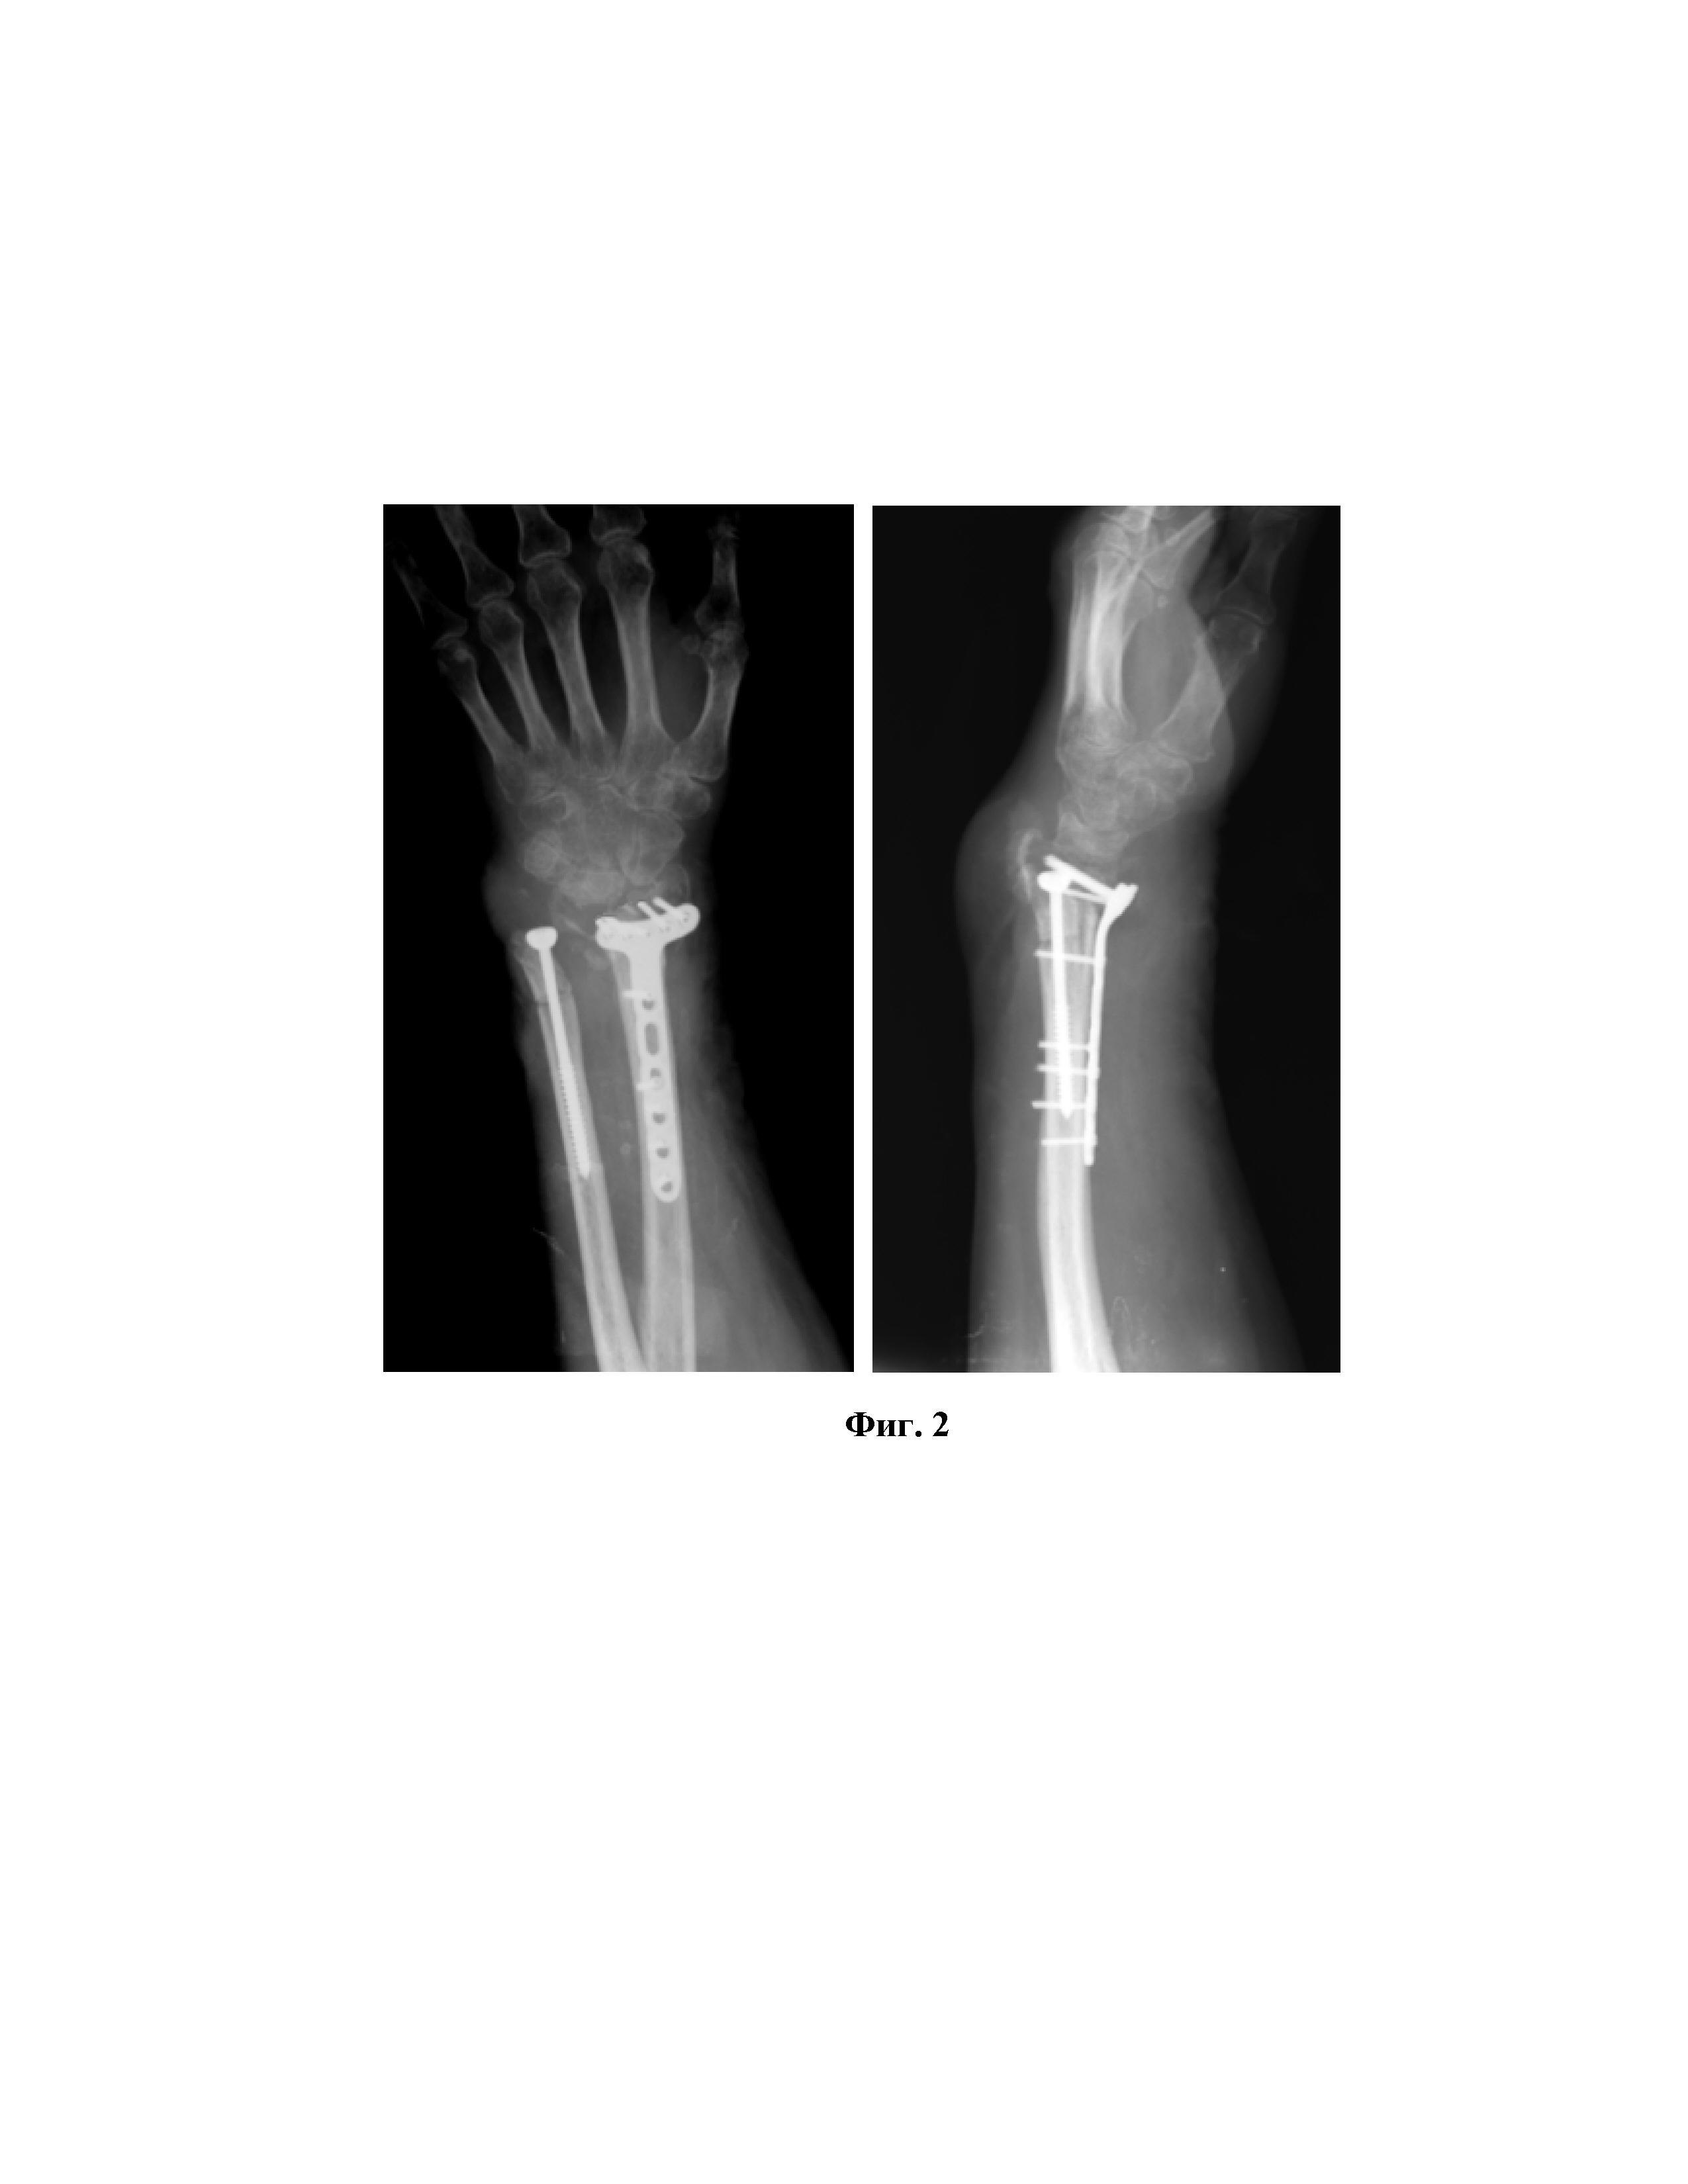

Изобретение относится к области медицины, а именно к травматологии и ортопедии для лечения посттравматической лучевой косорукости у взрослых с целью восстановления функциональных возможностей верхней конечности. При переломах лучевой кости в «типичном» месте, являющихся одним из наиболее встречаемых видов повреждений опорно-двигательного аппарата, часто происходит укорочение лучевой кости с формированием лучевой косорукости, коррекция которой возможна только оперативным путем. В настоящее время, несмотря на определенные успехи в лечении больных с данной патологий, при использовании любых существующих технологий хирургической коррекции лучевой косорукости, сроки лечения длительны, а количество случаев с положительным результатом колеблется в пределах 33,3-53,7%. Все способы коррекции посттравматической лучевой косорукости делятся на две группы, первая из которых ориентирована на восстановление длины лучевой кости и достижения, таким образом, косметического эффекта. Известны методики костно-пластической коррекции данной патологии, направленные на компенсацию укорочения посредством восполнения утраченной длины трансплантатом [Чрескостный остеосинтез при посттравматической лучевой косорукости/Пусева М.Э., Михайлов И.Н., Рудаков А.Н.//Сибирский медицинский журнал. 2009. №7. С. 107-110]. Одним из примеров данных методик является «Способ оперативного лечения приобретенной лучевой косорукости» [авторское свидетельство SU на изобретение №194249], направленный на постепенное растяжение латерального отдела предплечья до полного вправления головки локтевой кости с последующим замещением дефекта ауто- или гомотрансплантатом и фиксированием его компрессионным остеосинтезом. Однако устранение укорочения более 2,5 см методом аутопластики, в большинстве случаев невозможно, т.к. максимально вырастает риск отторжения трансплантата большого объема. При этом их длительная перестройка значительно удлиняет сроки лечения и реабилитации, а также сопровождается необходимостью иммоболизации конечности на долгий срок. Формирование аутотрансплантатов больших объемов затруднительно и сопряжено с дополнительной травматизацией. Известны также способы лечения укорочения лучевой кости методом дистракционного остеосинтеза с использованием различных модификаций аппаратов внешней фиксации [Бородин В.В. Лечение по Илизарову приобретенной лучевой косорукости: Автореф… дис. канд. мед. наук. Пермь. 1992. 23с.]. Однако при использовании данных технологий лечения были отмечены частые рецидивы, развитие контрактур, в том числе «когтеобразной кисти», ишемии мягких тканей, сосудистых и неврологических нарушений, обусловленных длительной дистракцией, и возникновение инфекционных осложнений, в частности в местах введения чрескостных элементов: спиц, стержней и т.д. Ко второй группе методик коррекции посттравматической косорукости относятся способы, направленные на восстановление нормальных анатомических межсегментарных пропорций путем укорочения локтевой кости. Одной из таких методик является проведение корригирующей остеотомии лучевой кости с резекцией дистального конца локтевой кости [Чрескостный остеосинтез при посттравматической лучевой косорукости/Пусева М.Э., Михайлов И.Н., Рудаков А.Н.//Сибирский медицинский журнал. 2009. №7. С. 107-110]. Однако при использовании данного способа выполняют удаление суставной поверхности локтевой кости, нарушая взаимоотношение суставных концов, снижая мышечную силу кисти вследствие сближения точек прикрепления мышц предплечья и значительно травмируя их в месте прикрепления к суставному концу локтевой кости во время выполнения резекции её фрагмента. Известно также упоминание о намерении лечения посттравматической косорукости путем укорочения локтевой кости Т.А. Бровкиной. Однако данное предложение было отвергнуто в связи с тем, что было направлено на лечение детской категории больных. По мнению ряда авторов, данные операции у детей не восстанавливают полностью функцию конечности и нарушают её дальнейший рост. Таким образом, существующие в настоящее время методики лечения посттравматической косорукости позволяют лишь частично улучшить анатомию верхней конечности, но не позволяют достичь максимально возможного функционального эффекта. Кроме того, данные литературы свидетельствуют о высокой частоте рецидивирования косорукости, ухудшении функции конечности в случаях применения известных оперативных методов лечения данной патологии. При лечении посттравматической деформации лучезапястного сустава у взрослых, обусловленной укорочением лучевой кости, следует руководствоваться совсем другими приоритетами. Первостепенное внимание должно уделяться снижению сроков нетрудоспособности, восстановлению функции, устранению болевого синдрома. Тем более, что в категорию больных с данной патологией зачастую входят люди трудоспособного возраста, а для верхней конечности в функциональном и косметическом плане допустимы укорочения до 8 см [Остеосинтез. Руководство для врачей. Ткаченко С.С. 1987]. Из всего вышесказанного можно сделать вывод, что потребность в разработке новой технологии лечения посттравматической косорукости, направленной на восстановление анатомических пропорций с минимизацией риска повреждения связочно-мышечного аппарата и сосудисто-нервных образований, высока, а наиболее близким аналогом к заявляемому изобретению можно считать любой из вышеуказанных аналогов, направленных на укорочение локтевой кости. Задачей заявляемого изобретения является разработка способа хирургической коррекции посттравматической лучевой косорукости у взрослых, позволяющего достичь полноценного функционального эффекта в наиболее короткие сроки с обеспечением восстановления анатомических взаимоотношений в лучезапястном суставе, минимизируя при этом возможность возникновения рецидива патологии и значительно снижая риск травмирования связочно-мышечного аппарата и сосудисто-нервных образований. Сущность заявляемого изобретения заключается в том, что в способе хирургической коррекции посттравматической лучевой косорукости у взрослых, включающем осуществление корригирующей остеотомии лучевой кости с устранением её деформации и фиксированием достигнутого положения посредством металлоконструкции, а также проведение резекции фрагмента локтевой кости, последнюю манипуляцию производят путем выполнения параллельных друг другу остеотомий в зоне шейки локтевой кости и проксимальнее с обеспечением удаления фрагмента локтевой кости протяженностью, равной величине укорочения лучевой кости, после чего головку локтевой кости транспонируют к её проксимальному фрагменту, сопоставляя их торцевые края, и фиксируют достигнутое положение посредством металлоконструкции. Технический результат заявляемого изобретения Такой технический прием, как выполнение укорочения локтевой кости путем удаления её фрагмента с обеспечением транспозиции головки локтевой кости, не резецируя последнюю, позволяет сохранить анатомические взаимоотношения в лучезапястном суставе, в том числе нормализуя радиоульнарный угол и не травмируя коллатеральную локтевую связку. Такой подход исключает возможность перерастяжения сухожилий и сосудисто-нервных образований, а, следовательно, снижает риск возникновения рецидива, например, по типу «когтеобразной кисти». В связи с отсутствием необходимости резекции головки локтевой кости данное изобретение позволяет значительно минимизировать травматичность тканей, улучшив функциональные результаты и сократив сроки реабилитации. При использовании данного способа лечения уже через 4-6 недель можно начинать разработку движений в суставе посредством ЛФК, также минимизируя возможность развития осложнений. Способ хирургической коррекции посттравматической лучевой косорукости у взрослых поясняется с помощью Фиг. 1-3, на которых изображено: на Фиг. 1 – рентгенограмма лучезапястного сустава больной К. при поступлении в стационар (прямая проекция); на Фиг. 2 – рентгенограмма лучезапястного сустава больной К. в раннем послеоперационном периоде (прямая и боковая проекции); на Фиг. 3 – рентгенограмма лучезапястного сустава больной К. через 3 месяца после проведенного хирургического вмешательства (прямая и боковая проекции). Способ хирургической коррекции посттравматической лучевой косорукости у взрослых осуществляют следующим образом. Посредством волярного разреза осуществляют хирургический доступ к лучезапястному суставу. Производят корригирующую остетомию лучевой кости в зоне деформации, после чего деформацию устраняют и достигнутое положение фрагментов кости фиксируют металлоконструкцией, в частности пластиной с блокирующими винтами. Затем производят разрез со стороны латерального края локтевой кости. Выполняют остеотомию в зоне шейки локтевой кости, в большинстве случаев на 1,5-2 см проксимальнее её головки. Проводят вторую остеотомию проксимальнее линии проведенной ранее остеотомии и параллельно ей, обеспечивая при этом удаление фрагмента локтевой кости протяженностью, равной величине укорочения лучевой кости. После головку локтевой кости транспонируют к её проксимальному фрагменту, сопоставляя их торцевые края. Фиксируют достигнутое положение посредством металлоконструкции. Пример Больная К. 62 лет поступила в НИИТОН СГМУ спустя 6 месяцев после получения травмы с диагнозом: «Посттравматическая деформация левого предплечья, неправильно сросшийся перелом дистального метаэпифиза левой лучевой кости, сгибательно-разгибательная контрактура левого лучезапястного сустава». После выполнения дополнительного обследования и предоперационной подготовки было проведено хирургическое вмешательство: корригирующая остеотомия левой лучевой кости на вершине деформации, укорачивающая остеотомия левой локтевой кости. После устранения деформации положение фрагментов лучевой кости было фиксировано пластиной с угловой стабильностью. Локтевая кость была укорочена на 2,5 см. Головка локтевой кости соединена с её проксимальным отломком, достигнутое положение фрагментов было зафиксировано посредством кортикального винта. При этом радиоульнарный угол после хирургического вмешательства составил 20 градусов. В послеоперационном периоде проводилась дополнительная иммобилизация в виде наложения жесткого ортеза на лучезапястный сустав. Проведение разработки движений в суставе с помощью ЛФК начали через 1 месяц после хирургического вмешательства. При проведении рентген-контроля через три месяца после хирургического вмешательства отмечали консолидацию перелома и восстановление функции лучезапястного сустава на 90%. Через год после хирургического вмешательства объем движений в лучезапястном суставе восстановился полностью.